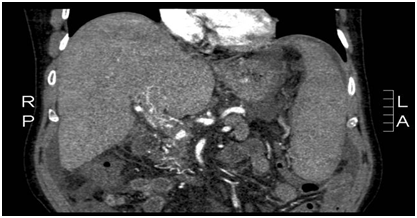

Laboratory showed elevated liverenzyms, especially cholestatic enzymes (AF en GGT) and elevated alpha-fetoprotein. Ultrasound en X-rays showed no abnormalities. During his stay in the hospital he deteriorates and developed ascites. And additional CT scan revealed a portal vein thrombosis (Figure 2). We could not find any other explanation for his complaints than recidive tumor with fever due to tumor necrosis. He was discharged from the hospital after 2 weeks and would be followed up on the outpatient clinic. He should receive palliative chemotherapy. Than in the outpatient clinic the serology of strongyloides and schistosomiasis became positive. The schistosomiasis infection is chronic. He was treated for the strongyloides infection with Ivermectine (one dose) and remarkably his liverenzyms normalized. The ascites disappeared and he had no fever anymore. Also the alpha-fetoprotein deteriorated. The tumor was not progressive for a few years without any therapy.

Figure 2 Portal vein thrombosis.

In this case the tumor marker deteriorates after treatment of the strongyloides infection. The treatment seems to have a positive effect on the tumor. We suspect that the strongyloides larvae were situated in the bile ducts and lead to cholestasis and inflammation, which explains the fever and so leading to portal vein thrombosis. The portal vein thrombosis disappeared after treatment of the strongyloides infection and all of the patient’s symptoms (Figure 3).

Figure 3 MRI after strongyloides infection therapy.